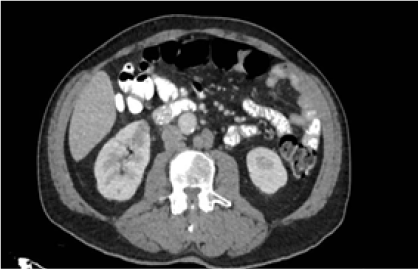

Radiográficamente, se evidenció radioopacidad en lóbulo superior izquierdo que desplaza ipsilateralmente el bronquio principal izquierdo, con criterios de atelectasia lobar superior izquierda (Figura 3). La tomografía resaltó interrupción abrupta del bronquio del lóbulo superior izquierdo asociado a lesión de 3,7 x 3,2 cm que condiciona atelectasia del lóbulo superior izquierdo en relación con proceso neoformativo (Figura 4), nódulos pulmonares de distribución aleatoria, adenopatías cervicales, mediastínicas y retroperitoneales, también lesiones nodulares hepáticas y una lesión que realza con contraste en riñón derecho. Se identificaron adenopatías en los niveles II, III y IV derecho y II, III , IV izquierdo. Adicional lesiones de densidad intermedia en el riñón derecho que realzan en la fase contratada (Figura 5A). Lesiones blásticas con probable relación con depósitos secundarios en T5, T10, T11, L3 Y L5 (Figura 5B). Biopsia de la lesión es positiva para adenocarcinoma pulmonar con patrón histológico tipo acinar. Se identificó deleción del exón 19 de receptor del factor de crecimiento epidérmico (EGFR).

Figura 5.

Izquierda. Lesión metastásica de densidad intermedia en el riñón derecho que realza en la fase contratada

Derecha. Lesiones osteolíticas en cuerpo vertebral L2.

Fuente: Servicio de Radiología, Complejo Hospitalario Arnulfo Arias Madrid.